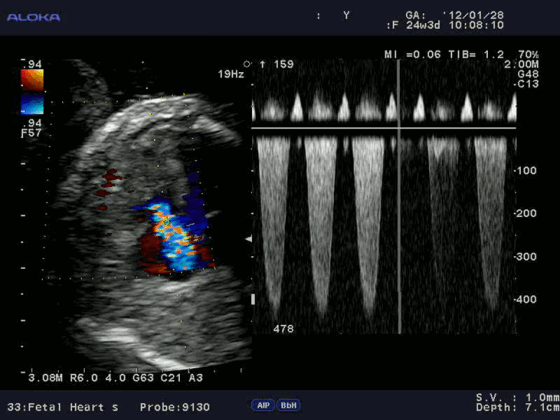

Техническая справка: Эхокардиография с допплерометрией и ЦДК

Эхокардиография с допплерометрией и цветным допплеровским картированием (ЦДК) – это сочетание обычного двумерного ультразвукового сканирования сердца для анализа его анатомии с допплерометрией. Эффектом Допплера называется физическое явление изменения частоты ультразвука при отражении его от движущихся объектов. Допплерометрия позволяет оценить ток крови, его направление, скорость и характер, а в сердце выявить недостаточность и стеноз клапанов, отрывы хорды и т.д. Сочетание обычного двумерного серошкального УЗИ с допплерометрией плюс добавление цветовой кодировки потоков крови (от УЗ-датчика и к нему) – это цветное допплеровское картирование. С его помощью наши специалисты сразу видят патологические забросы крови (из полости левого желудочка во время систолы в левое предсердие при недостаточности митрального клапана).

Для облегчения выявления турбулентного движения (завихрений) существует порог скорости, выше которого происходит изменение цвета (во многих аппаратах это зелены). «Мозаичный» узор на участке турбулентного потока позволяет легко установить регургитацию (смену направления движения), что помогает определить степень недостаточности клапанов.

Так, например, эхокардиография с допплерометрией и цветным допплеровским картированием (ЦДК), которая является сочетанием 2D и М-режимов с допплерометрией, очень полезна при оценке митрального стеноза. Первые два способа визуализации позволяют заподозрить кальцификацию клапана (аномальное движение его створок).

Допплерометрия демонстрирует при этой патологии повышенную скорость кровотока (признак сужения) и может быть использована для оценки «эффективной площади отверстия» (степени выраженности стеноза).